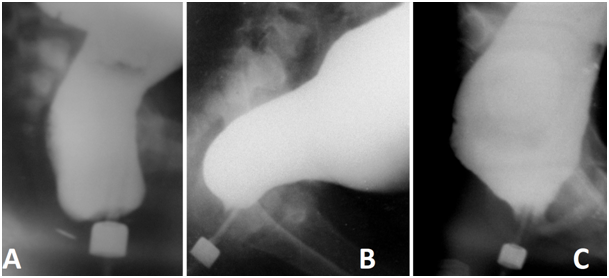

Figure 7 Lateral radiographs of patients with different diseases. The true width of the marker near the anus is 1.6 cm.

A) A 1.5-year-old girl with vestibular fistula during anal canal opening. The width of the rectum is 3.7 cm. The maximum limit of the norm for children under 3 years old is -2.8 cm. Conclusion: Anorectal malformation with ano-vestibular fistula and megarectum. The distance between the distal wall of the anal canal and the button near the anal dimple is 0.5 cm. B) A 12-year-old boy with chronic constipation. The rectum is wider than the maximum limit of the norm (6 cm vs. 4.6 cm), but the recto-sigmoid index is < 1. The length of the anal canal is at the lower limit of the norm (3 cm ≈ 3.1 cm). The shape of the rectum as in newborns. There is no horizontal branch of the rectum. This indicates a violation of innervation. Puborectalis is not contracted due to the absence of ganglia in the rectum. Conclusion: Hirschsprung disease with a short area of ​​agangliosis not complicated by enterocolitis. ,C) A 9-year-old boy with chronic constipation and encopresis. The rectal width is 9.4 cm vs. the maximum normal limit of 4.1 cm. The anal canal length is 1.8 cm vs. the minimum normal limit of 2.6 cm. Conclusion: Functional constipation of the 3rd stage, stretching of the pelvic floor muscles (descending perineum syndrome).